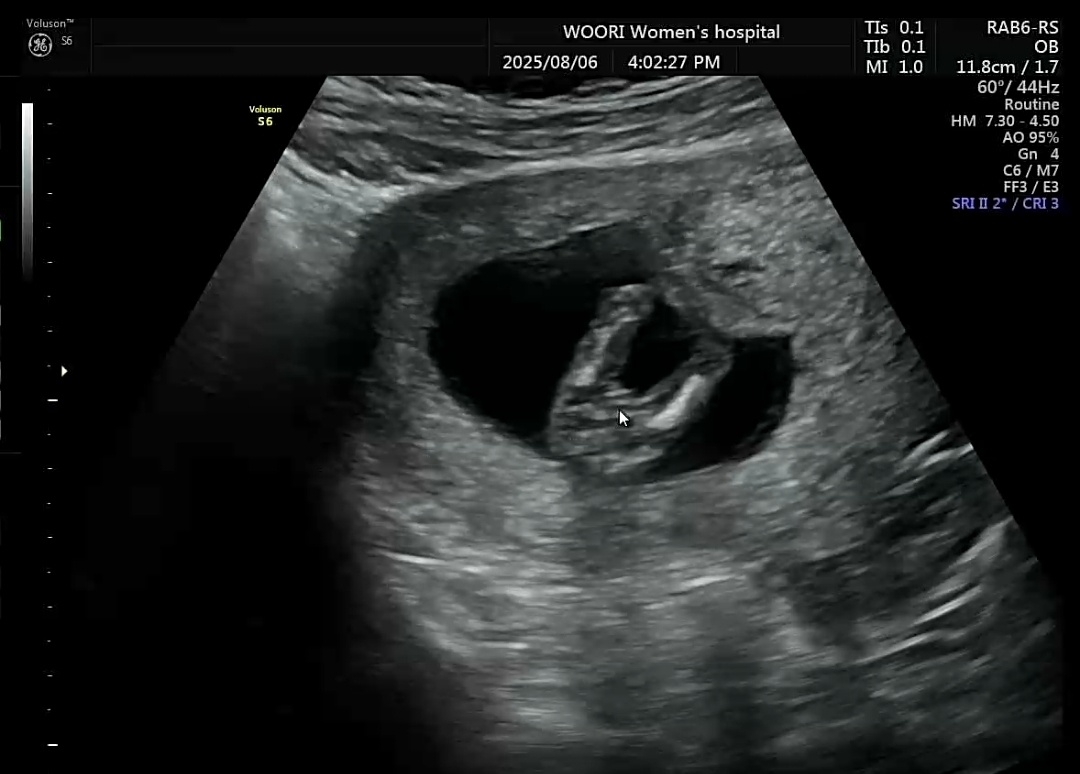

13주 4일차) 아기 봐주세요~

14주크기 아가에요 :) 선생님이 아직 아무것도 안보이긴한대요